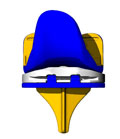

Protesi di ginocchio

Quando il quadro clinico è più grave, siamo di fronte ad una artrosi diffusa. Il trattamento consiste nel sostituire la cartilagine irreversibilmente malata con protesi di nuova generazione in titanio e prevede la sostituzione dell’osso degenerato con mascherine di metallo più o meno grandi in base alla gravità del quadro.

Quando il quadro clinico è più grave, siamo di fronte ad una artrosi diffusa. Il trattamento consiste nel sostituire la cartilagine irreversibilmente malata con protesi di nuova generazione in titanio e prevede la sostituzione dell’osso degenerato con mascherine di metallo più o meno grandi in base alla gravità del quadro.

Nel ginocchio si parla di protesi monocompartimentali quando si sostituisce solo una parte del ginocchio, mediale o laterale; di protesi totali o artroprotesi quando si sostituisce tutta l’articolazione con o senza la protesizzazione della rotula.